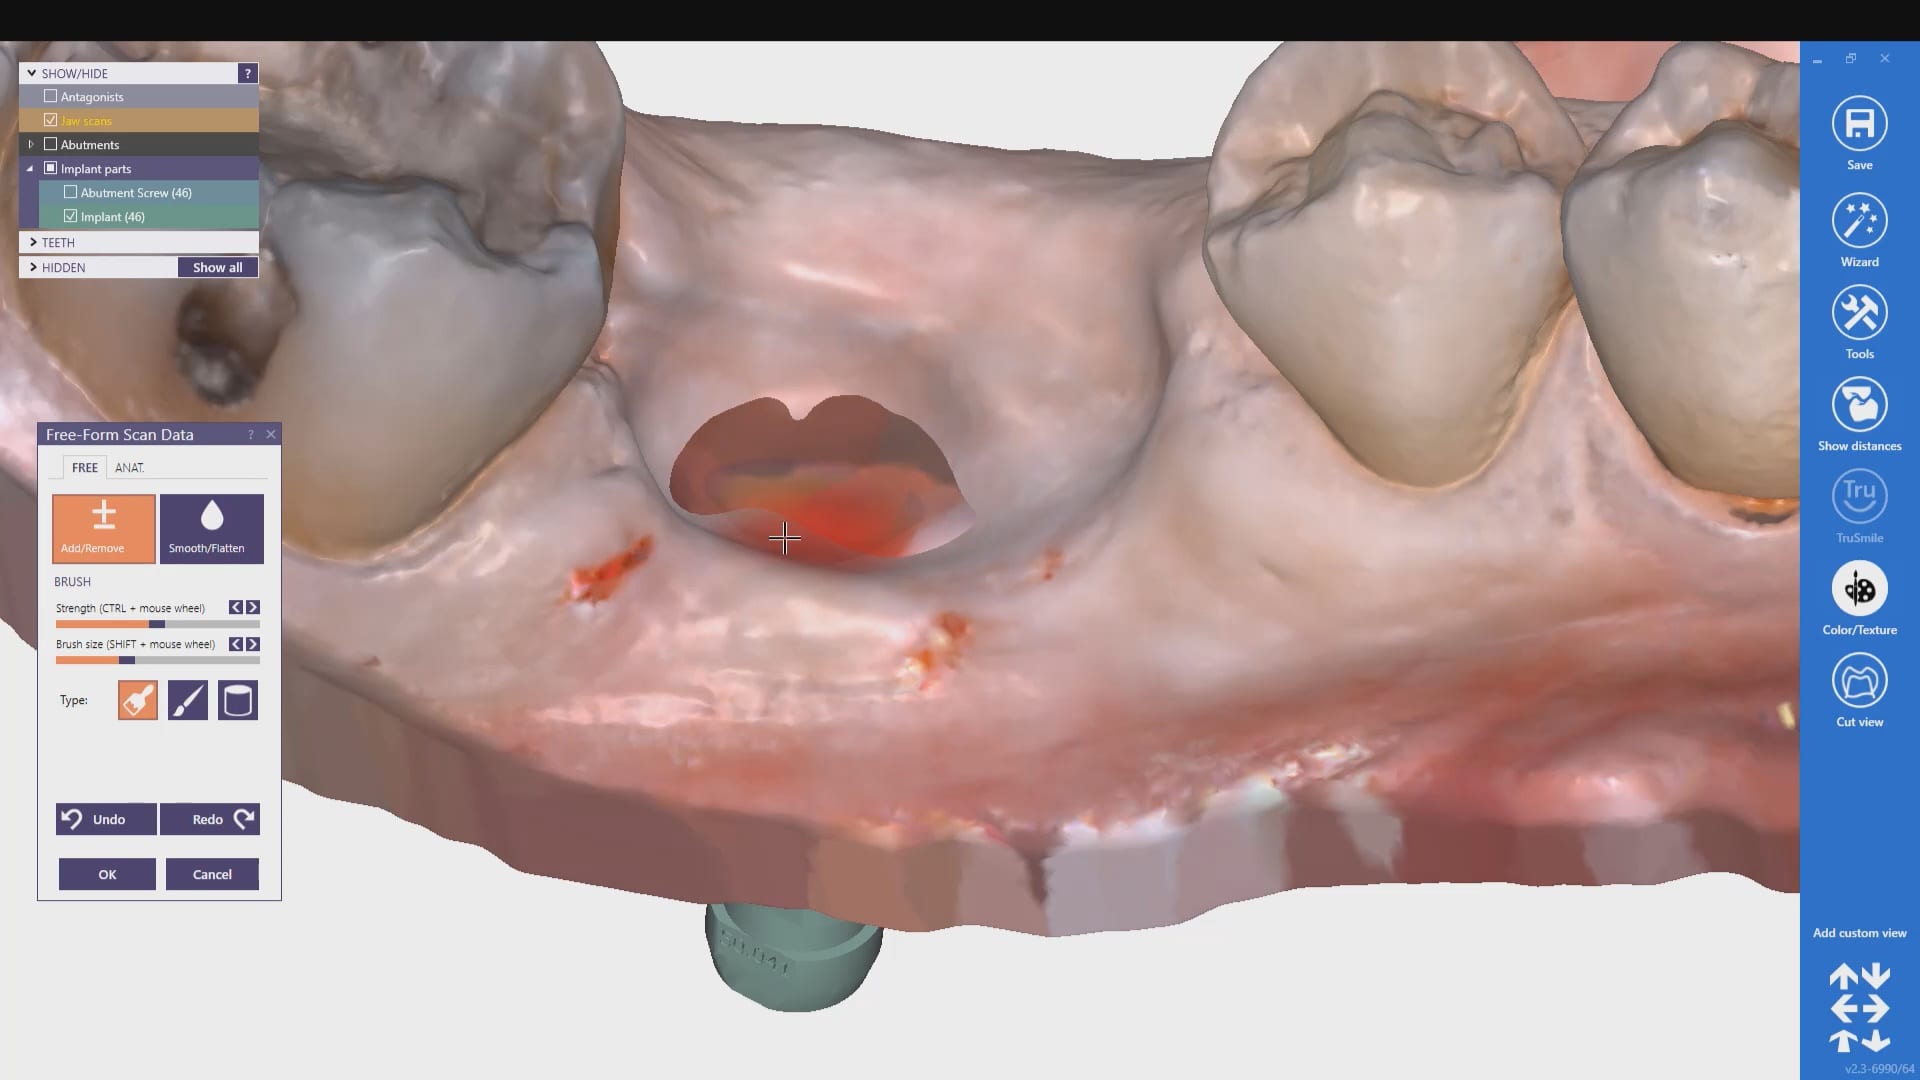

Single Implant Scanbody Digital Impression with the Medit i500 Intra-Oral Scanner

February 4, 2020This is a preview of a single unit case that was scanned using the Artificial Implant Suprastructure Identification System of the Medit Software. To see the full case follow this […]